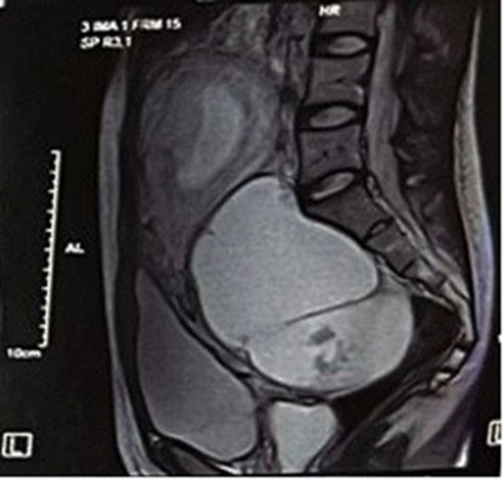

ულტრასონოგრაფია: საკვერცხის დაბალდიფერენცირბული სეროზული კარცინომის დიაგნოსტიკის ერთ-ერთი მნიშვნელოვანი მეთოდი ულტრასონოგრაფიაა, ადრეული სავარაუდო დიაგნოზის დასასმელად, ჰისტომორფოლოგიამდე მისი გამოყენება ბევრ ინფორმაციას იძლევა. ულტრასონოგრაფიულად შესაძლოა დავინახოთ საშუალო დონის რთული ცისტური წარმონაქმნები მყარი კომპონენტებითა და კალციფიკაციებით. იშვიათად არის მჭიდროდ ვასკულარიზებული, რაც გამიჯვნის საშუალებას იძლევა HGSOC-გან.

კომპიუტერული ტომოგრაფია: CT მეტასტაზების შეფასებასა და დიაგნოსტიკაში ძირითად გამოსახულებით მეთოდად მოიაზრება, იდეალურად შეგვიძლია ლიმფადენოპათიისა და პერიტონეალური მეტასტაზების ამოცნობა(სიზუსტე 89%), CT-ზე LGOSC ვიზუალიზდება, როგორც დიდი, კომპლექსური კარგად შემოსაზღვრული ცისტური წარმონაქმნი პაპილარული გამონაზარდებით და მყარი კომპონენტებით,შეიძლება იყოს უნილატერალური ან ბილატერალური. ხშირად აღინიშნება კალციფიკაციები როგორც ადნექსალურ მასაში, ასევე პერიტონეალურ მეტასტაზებში.

მაგნიტო-რეზონანსული ტომოგრაფია:MRI არის უმნიშვნელოვანესი ინსტრუმენტი LGSC-ის დიფერენცირებისთვის სხვა ადნექსალური მასებისგან, მაგალითად:

- LGSOC აქვს უფრო დაბალი ADC(apparent diffusion coefficient), ვიდრე SBT-ს, რაც მეტყველებს უფრო მეტ ცილოვან/ცხიმოვან კომპონენტზე და უჯრედულობაზე.

- უფრო მაღალი ADC, ვიდრე HGSC-ს (HGSC როგორც წესი უფრო უჯრედული და აგრესიულია, რაც ზრდის წყლის მოძრაობის შეზღუდვას და ამცირებს ADC-ს)

26 წლის ორსულმა პაციენტმა მიმართა გინეკოლოგიურ განყოფილებას, საკვერცხეზე დიაგნოსტირებული წანაზარდის გამო. ულტრასონოგრაფიულად გამოვლინდა დიდი ზომის (122მმ*104მმ*90მმ)ჰეტეროგენული წარმონაქმნი, ვასკულარიზებული კედლებით.MRI-ზე ვიზუალიზდა მარჯვენა საკვერცხის ცისტური წანაზარდი და დაიგეგმა ოპერაცია. ლაპარატომიული მიდგომით 27-ე კვირაზე განხორციელდა მარჯვენამხრივი სალფინგოოფორექტომია, მასალის ჰისტოპათოლოგიური კვლევით გამოვლინდა LGSOC, ლიმფოვასკულარული ინფილტრაციის გარეშე. მშობიარობა 36-ე კვირას ჩატარდა გართულებების გარეშე და 46-ე დღეს დაიგეგმა ლაპარასკოპიული კვლევა, რის შედეგადაც აღებულ ბიოფსიურ მასალებში სიმსივნური უჯრედები არ გამოვლინდა. პაციენტის რეაბილიტაცია და მკურნალობა დამაკმაყოფილებლად მიმდინარეობს რეციდივების ნიშნების გარეშე.